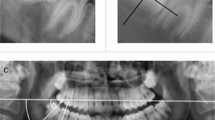

Basic procedure: A Markov process model was developed to model eruption of lower third molars using a 1-year time increment based on simulated eruption data relating to 100 lower third molars. This model was tested using a Monte Carlo simulation and compared with eruption patterns of 973 actual lower third molars. Statistical analysis of the differences between the simulated and actual groups was undertaken.

Main findings: There were no differences between the simulated and actual data other than for the subgroup aged 30-34 where the simulation overestimated the probability of parteruption and underestimated the probability of uneruption and full eruption.